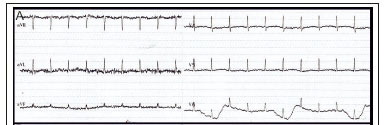

A 41-year-old man was admitted to the intensive care unit at Steve Biko Academic Hospital with acute pancreatitis, suspected clinically based on a raised amylase level (450 U/L; reference range: 20 - 104 U/L), and later confirmed on a computed tomography (CT) scan. Pancreatitis was due to the use of herbal medication and a cytomegalovirus infection (viral load: 5472 U/L). The patient was HIV co-infected (stage 4 according to World Health Organization staging guidelines), but highly active antiretroviral therapy had not been initiated. In addition, he had stage 3 chronic kidney disease (CKD), proven on biopsy to be due to HIV-related focal segmental glomerulosclerosis, complicated by anaemia and secondary hyperparathyroidism. The patient developed severe, acute hypocalcaemia (corrected serum calcium level: 1.09 mmol/L; reference range: 2.15 - 2.50 mmol/L), precipitated by pancreatitis-induced saponification and aggressive administration of saline. Clinically, this presented as a positive Trousseau's sign during blood pressure measurement and a prolonged corrected QT (QTc) interval (360 ms) on the electrocardiograph upon admission (Fig. 1A). The patient became unexpectedly unstable 24 hours post admission and developed acute pulmonary oedema that required ventilation. An electrocardiogram performed at this time revealed ST elevation in keeping with an acute myocardial infarction (Fig. 1B). Serum troponins were initially within the normal range (40 ng/L), but later became markedly elevated (peak: 4 358 ng/L). His urine output remained >1 mL/kg/h.

An acute ST-elevation myocardial infarction was diagnosed and a thrombolytic agent was prescribed, while intravenous calcium replacement had been initiated as part of his resuscitation. The patient stabilised before the thrombolytic agent could be administered, with complete resolution of the ST elevation and no residual Q waves (Fig. 1C).